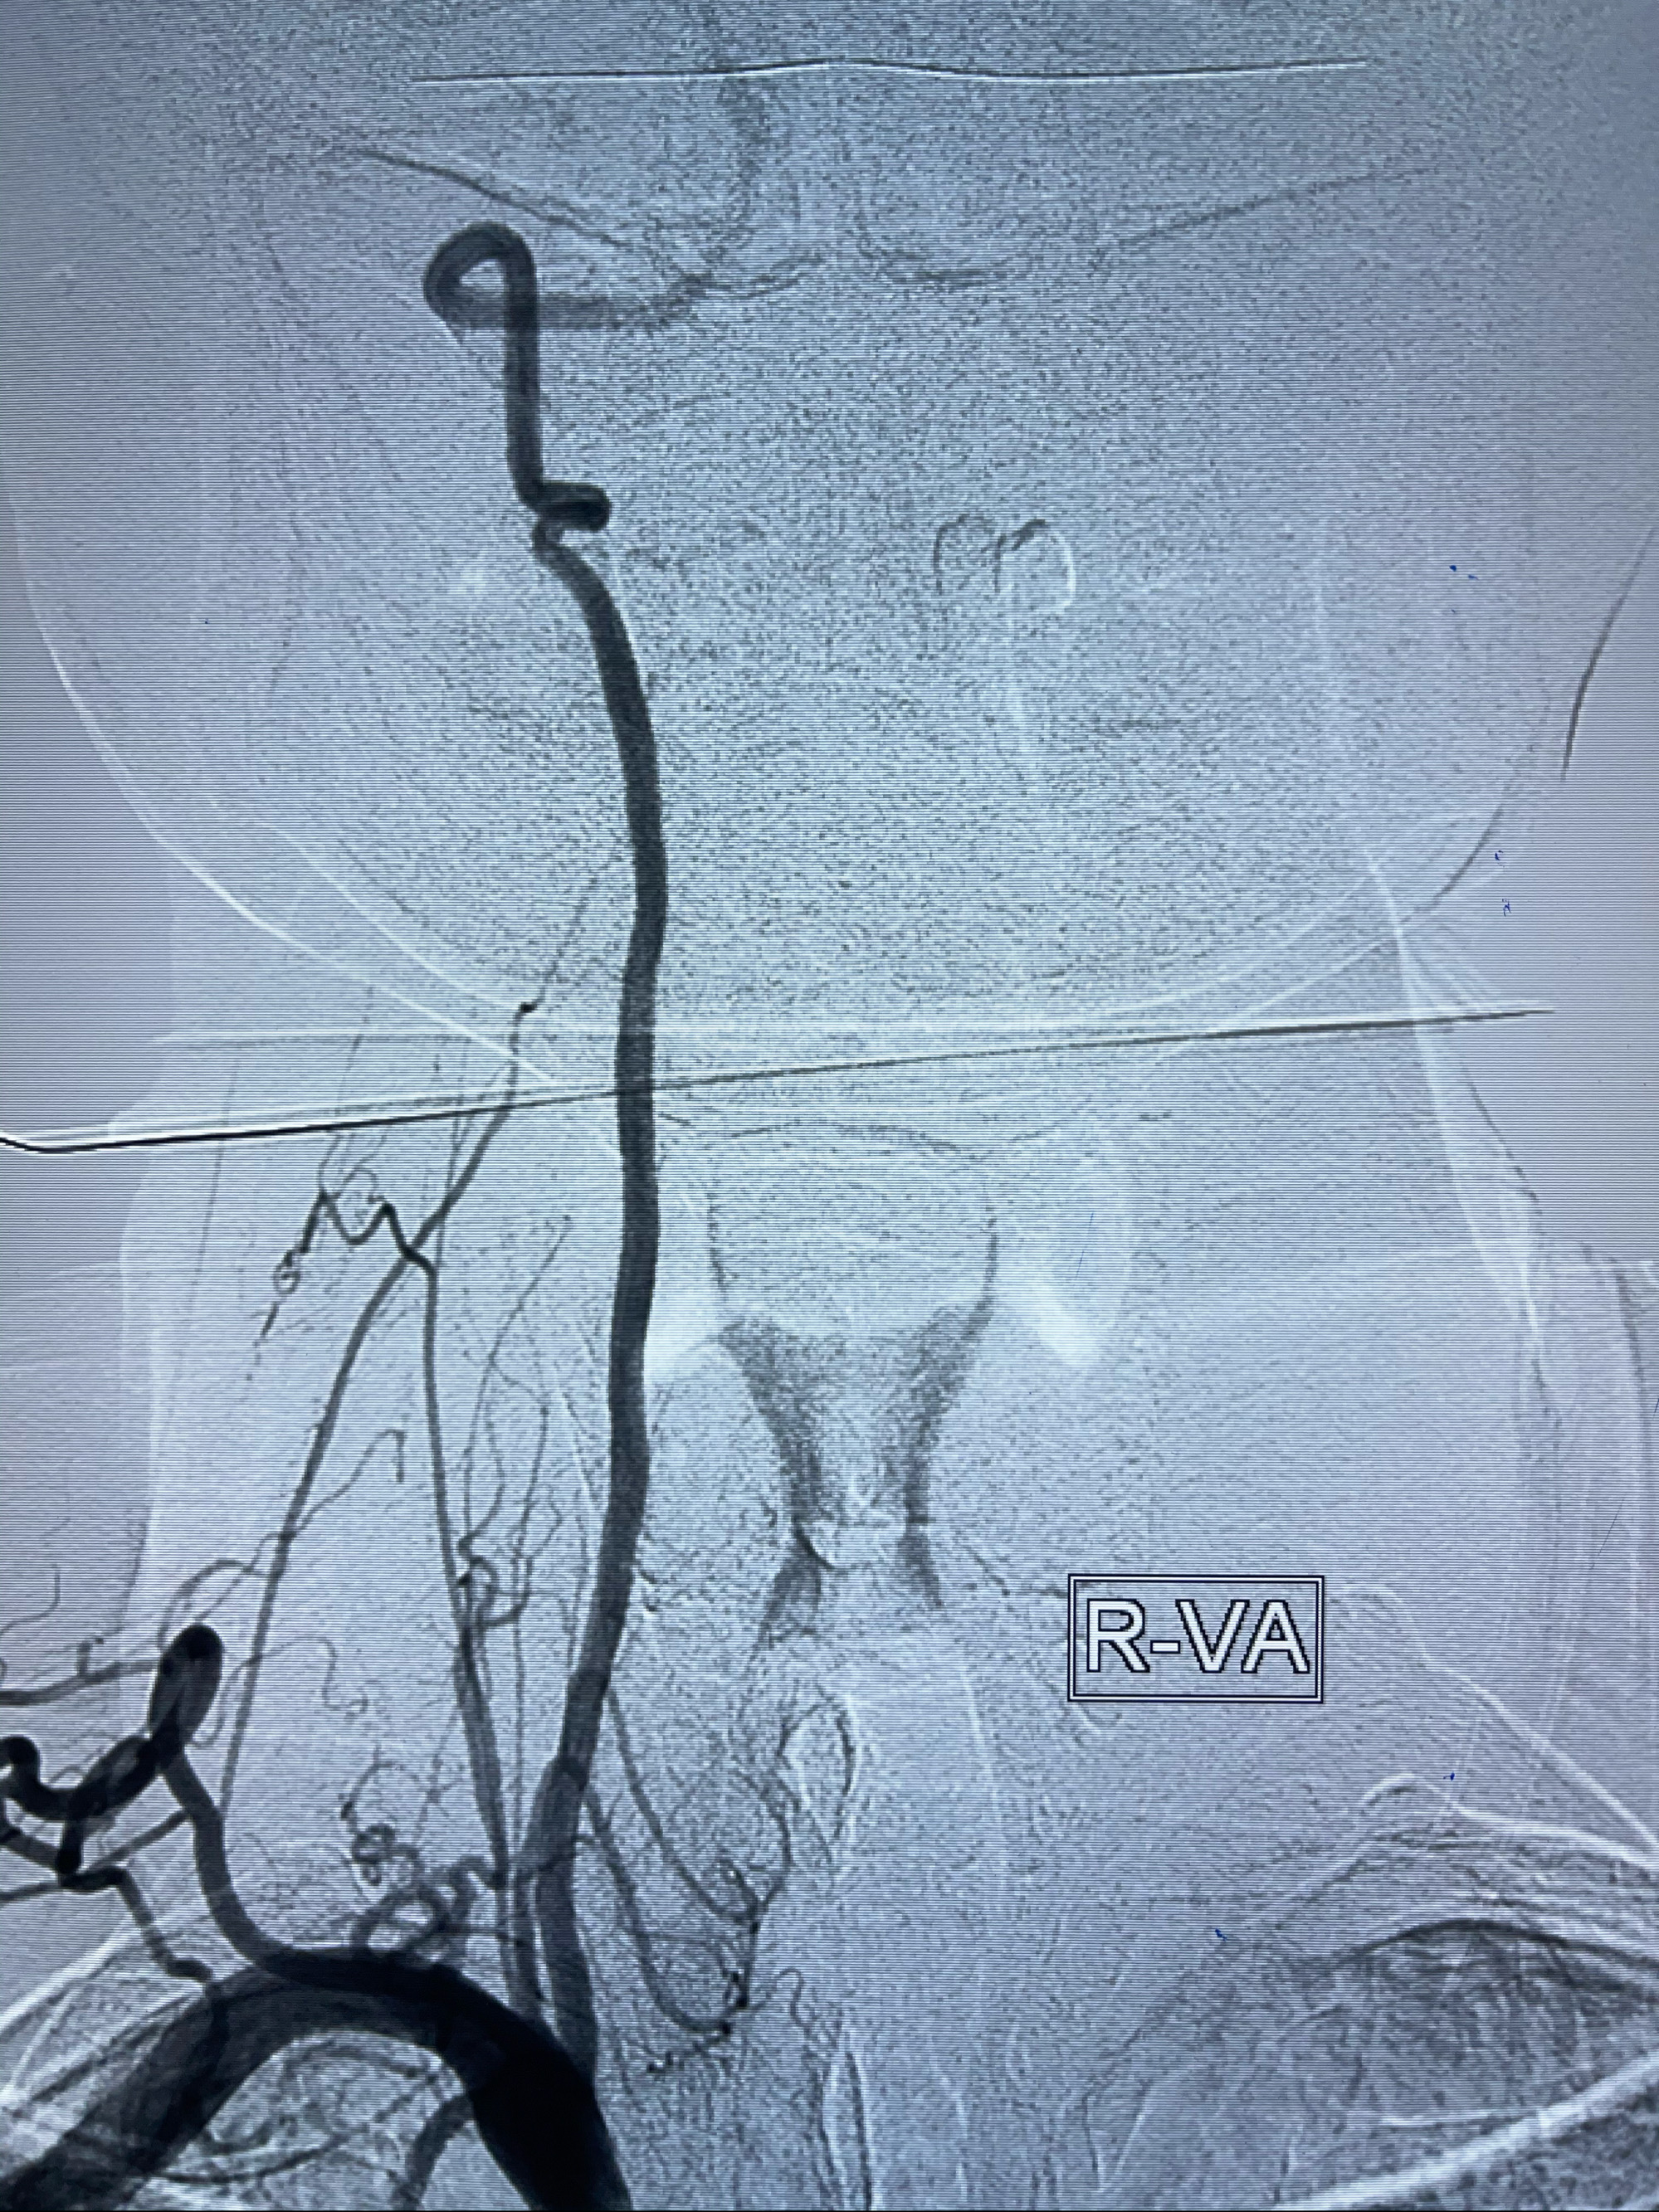

左侧椎动脉V4夹层动脉瘤多支架辅助栓塞:

1.Enterprise4.0-23mm;

2.Tubridge3.5-30mm密网支架

DA导引导管到位

支架到位

支架释放,透视下

麻醉苏醒佳,遵嘱动作。

术后即刻CT